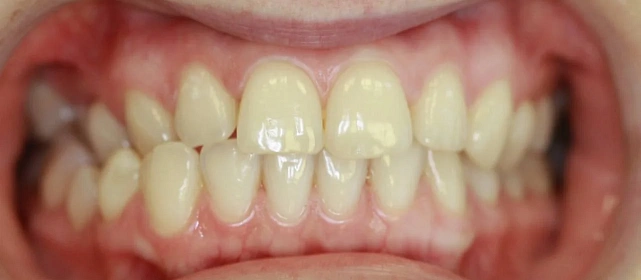

Нарушение соотношения челюстей и неправильное положение зубов — зубные ряды смыкались некорректно, зубы стояли со смещением.

Зубы выровнены, смыкание нормализовано. Установлены несъёмные ретейнеры на обе челюсти, сняты сканы для ретенционных кап.

Проблема: Пациентку не устраивало положение зубов и то, как смыкаются челюсти. Зубы стояли неровно, ряды сходились неправильно.

Решение: Поставили прозрачные элайнеры Click — начали с компактного набора из 20 кап. Основной комплект сделал основной объем работы, но для финальной доводки понадобился дополнительный набор из 10 кап. Итого 30 кап за 23 месяца. Результат — зубы на месте, смыкание в норме. Зафиксировали ретейнеры на обе челюсти, сняли сканы для ретенционных кап.